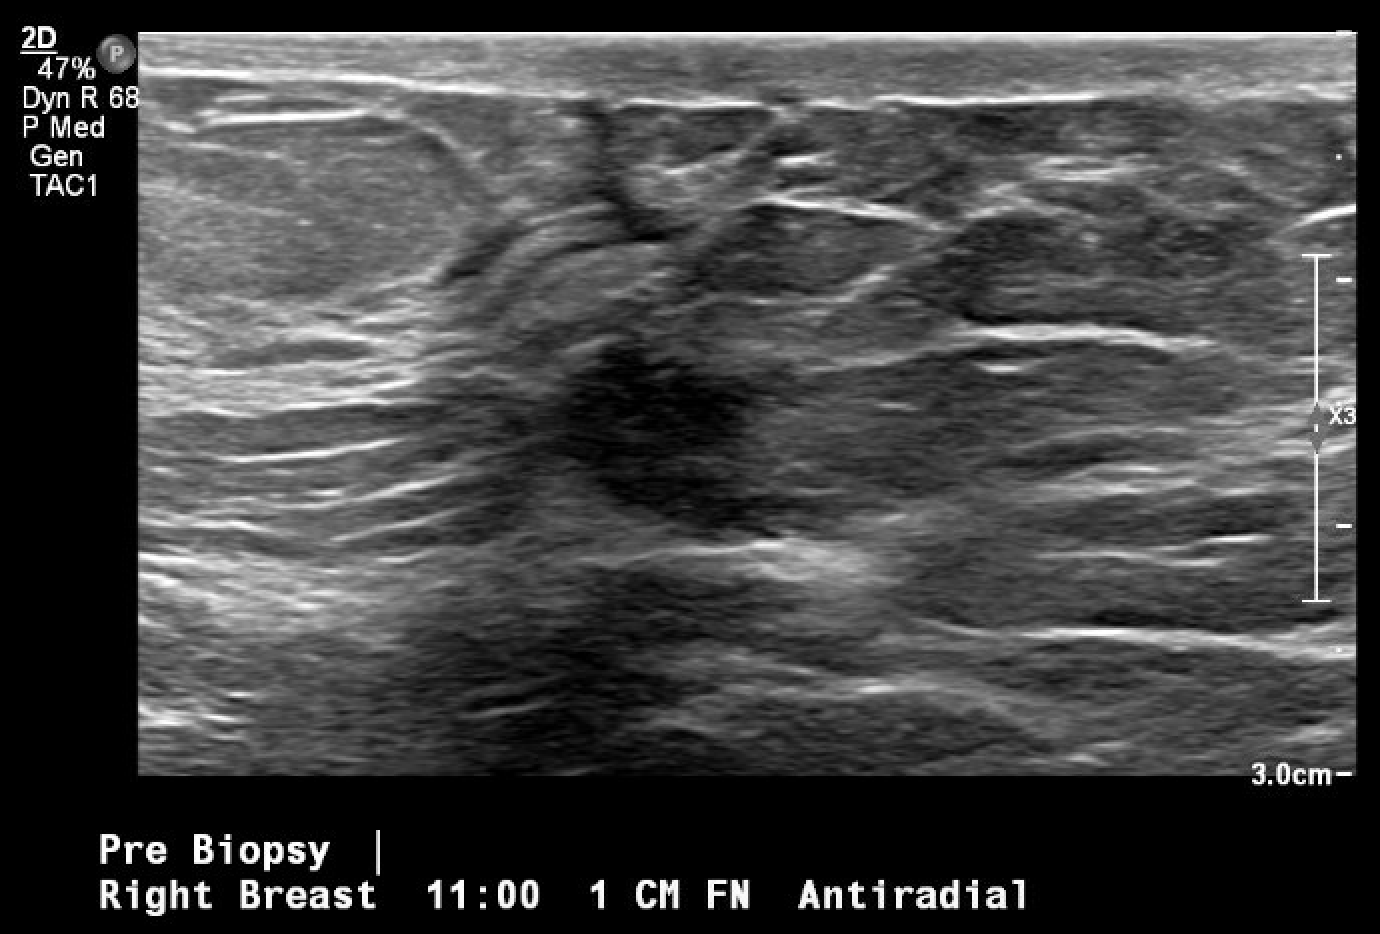

Se trata de una mujer premenopáusica de 46 años, sin antecedentes médicos o quirúrgicos, que acudió inicialmente a la clínica de cirugía mamaria después de que su mamografía anual de cribado descubriera una masa mamaria derecha no palpable de 0,6 x 0,8 x 0,7 cm a las 11 horas (oc), a 1 cm del pezón (FTN) (Figura 1). Se sometió a tres mamografías de detección previas sin ningún hallazgo notable. La mamografía de tamizaje se declaró no concluyente (BI-RADS 0) y se completó una ecografía mamaria con hallazgos similares. Una conversación más detallada con la paciente reveló que se había observado una secreción sanguinolenta en el lado derecho de su sostén en los últimos meses, pero no había otras preocupaciones o síntomas. Ante los hallazgos imagenológicos no concluyentes, se decidió realizar una mamografía diagnóstica para una valoración más específica (Figuras 2a y 2b) tras una biopsia con aguja gruesa guiada por ecografía y la colocación de un clip de localización para el diagnóstico tisular (Figura 3). La anatomía patológica reveló un papiloma intraductal con hiperplasia ductal y una metaplasia apocrina sin atipia. Dada su continua secreción sanguinolenta del pezón, hubo preocupación por posibles células premalignas subyacentes (discutidas más adelante); Por lo tanto, se recomendó que la paciente se sometiera a una mastectomía parcial. La masa permanecía inpalpable; por lo tanto, se colocaría un Savi Scout justo antes de la intervención operativa para ayudar a localizar el área de interés.

Figura 3. Localización y biopsia guiadas por ecografía de la masa mamaria en cuestión, observada por primera vez en una mamografía de detección. La imagen posterior a la biopsia incluye los cambios tisulares típicos que se observan una vez que se realiza una biopsia con aguja gruesa (marca de hash).